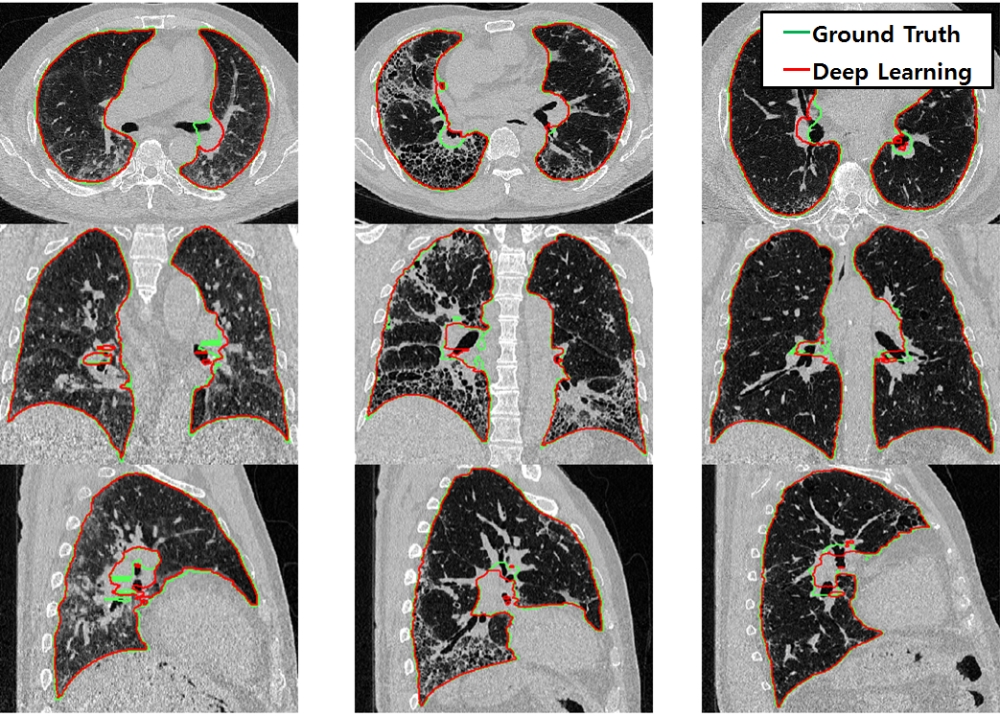

의료영상 분할이란 단층으로 촬영된 CT(컴퓨터단층촬영)나 MRI(자기공명영상) 같은 진단용 의료영상에서 체내 장기들과 종양 등의 경계선을 명확하게 그려 구분해내는 것을 말한다.

서울아산병원 융합의학과 김남국 교수가 이끄는 의료영상지능실현연구실(MI2RL, Medical Imaging Intelligent Reality Lab)은 카카오브레인과 뷰노와 함께 CT, MRI 등 의료영상에서 체내 장기나 질환의 위치를 인지하는 인공지능 네트워크 E-Net과 체내 장기와 질환의 경계선을 정확하게 그려 분할하는 P-Net 인공지능 네트워크를 결합한 Cascade U-Net을 자체적으로 개발해 대회에 참가했다.

그 결과 김 교수팀은 약 80%의 정확도로 체내 장기와 질환을 3D 이미지로 구현해냈다. 또한 1초당 약 100장의 의료영상을 분할해내 약 10초 이내에 장기의 상태를 3D 이미지로 나타냈다.